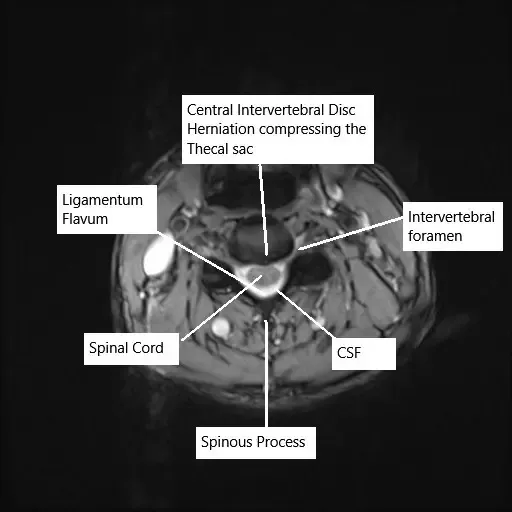

Axial section of the cervical spine showing disk herniation on MRI.

Diagnosis is confirmed through clinical examination and imaging studies. An MRI is the gold standard for identifying disc herniation, disc degeneration, and nerve root compression. In cases of cervical or lumbar pain, MRI scans will reveal the location and extent of the herniation, the condition of the discs, and any impingement on the nerves or spinal cord.